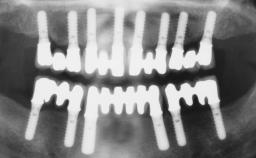

| Timing of placement | Immediate Placement (extraction sockets) (Type I) |

| Available apical bone to achieve primary stability | Sufficient height ( ≥ 4 mm) and width (> 2 mm around apex of planned implant) |

| Socket walls | Intact |

| Thickness of buccal wall | less than 2 mm |

| Anticipated residual defect after implant placement | 2 mm or less |